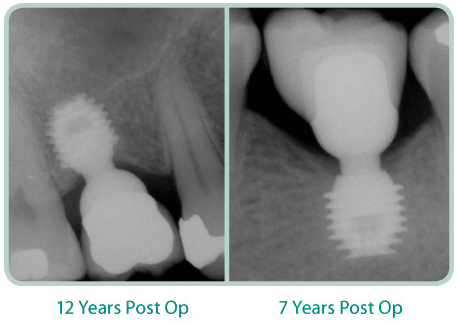

THE BICON DESIGN is driven by simplicity. A cornerstone of its simplicity is SHORT® Implants. When the Bicon system was first introduced in 1985, its 8.0mm length implants were considered quite short—most other implants were at least 12-14mm and sometimes 18-20mm long! Since then, the natural progression of Bicon’s design philosophy has resulted in 5.0mm and 6.0mm SHORT® Implants all with proven clinical success.